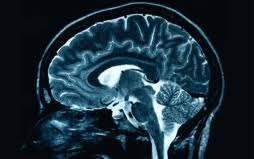

Agysejtek adnak betekintést a Down-Szindrómába

Laboratóriumban növesztett agysejteken vizsgálták a Down-szindróma kialakulásának okát. A betegséget okozó hibás gén az értelmi fogyatékosság mellett számtalan fizikai jelet is produkál. A vizsgálat megállapította, hogy a betegek agysejtjei közötti kommunikáció jóval lassabb, mint egészséges társaiknál - írja a BBC.

Jelen tanulmányt Anita Bhattacharyya, a Wisconsin-Madison Egyetem neurológusa vezetésével készítették. A kísérleti vizsgálat során két Down-szindrómás páciens bőrsejtjéből laboratóriumban őssejt segítségével növesztettek agysejtet. Ez az egyik módja ugyanis annak, hogy megnézzék mi történik a betegek agysejtjeivel fejlődés közben, ami a Down-szindrómát okozza.

Az egyik jelentős eredmény az volt, hogy csökkent a kapcsolat az idegsejtek között. 'Kevesebben és lassabban közlekednek' - mondta Anita Bhattacharyya. Az agysejtek szinapszisokon keresztül kommunikálnak egymással. A szinapszisok számát és aktivitását tekintve a Down-szindrómásoknál ez 60 százalékkal kisebb, mint az egészséges embereknél.